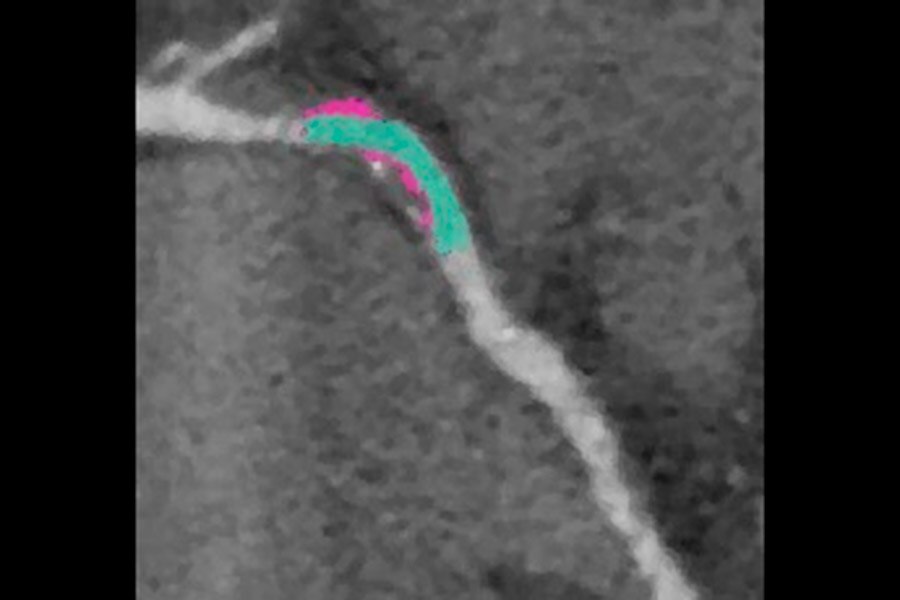

Visualization of the lumen on calcified RCA. BMI 28, HR 57